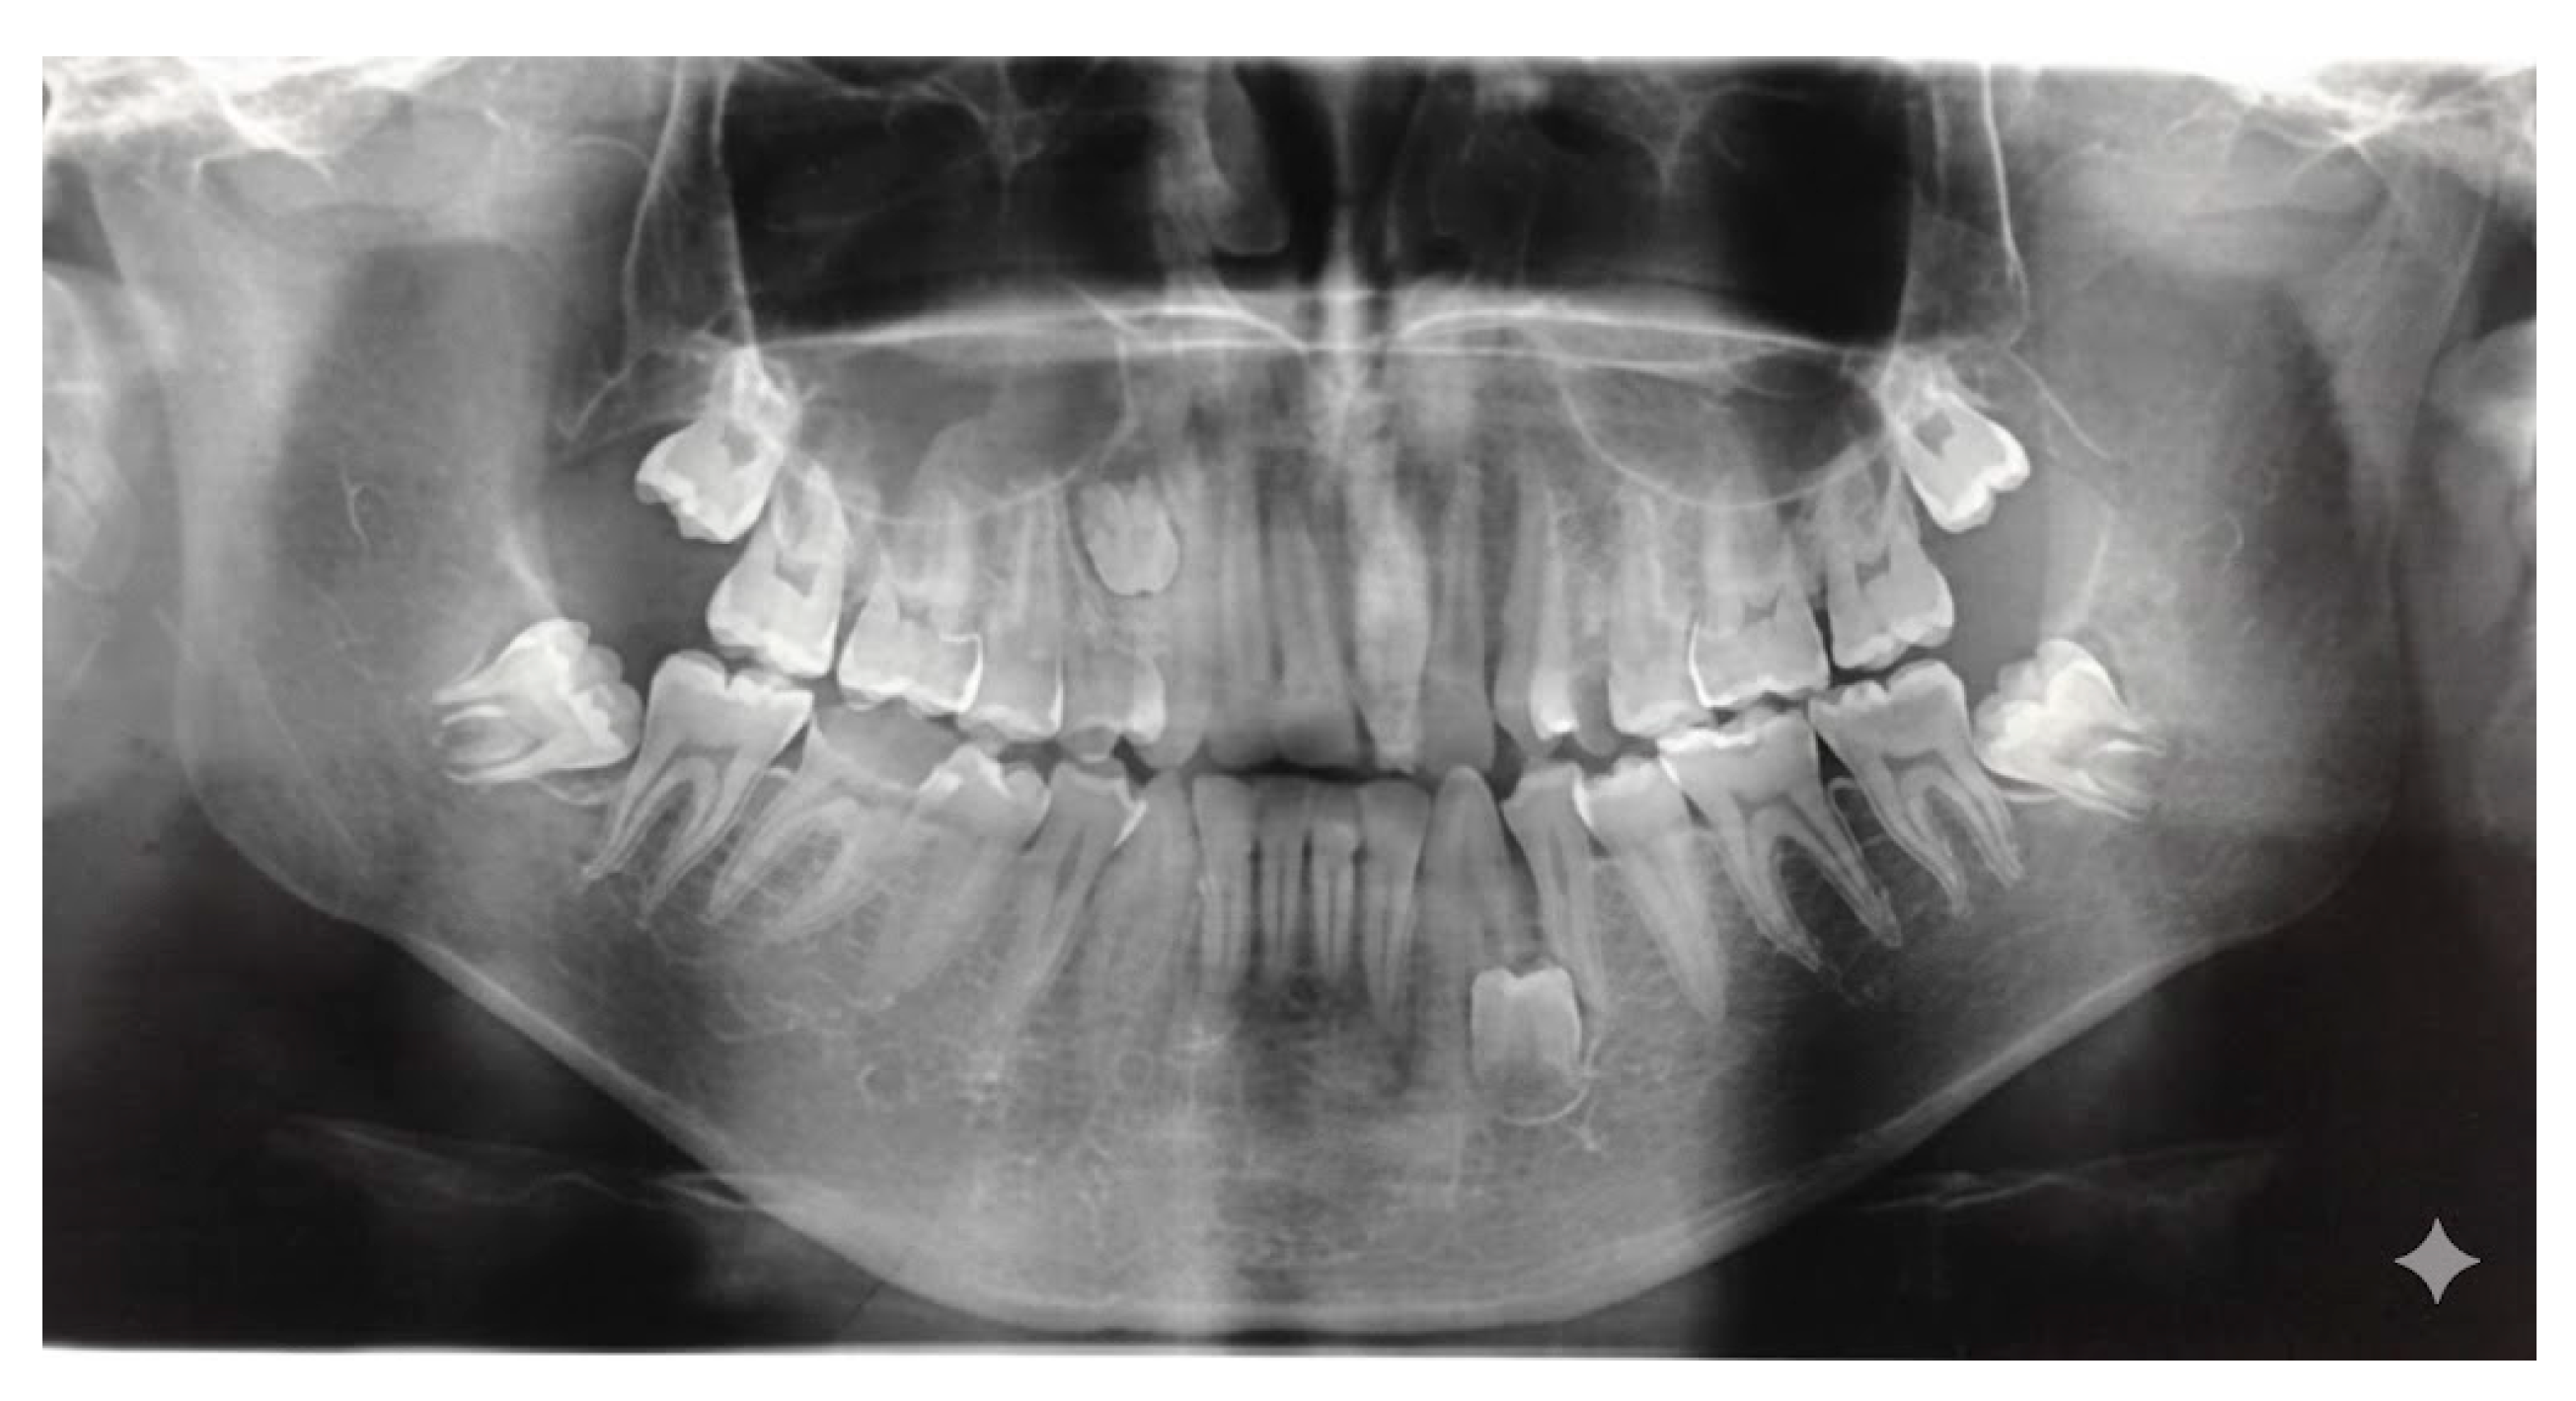

The presence of supernumerary teeth (Figure 1) is not a morphological curiosity but a potential source of diverse pathological complications [1,2,3,4].

Figure 1. Supernumerary teeth in the upper left quadrant.